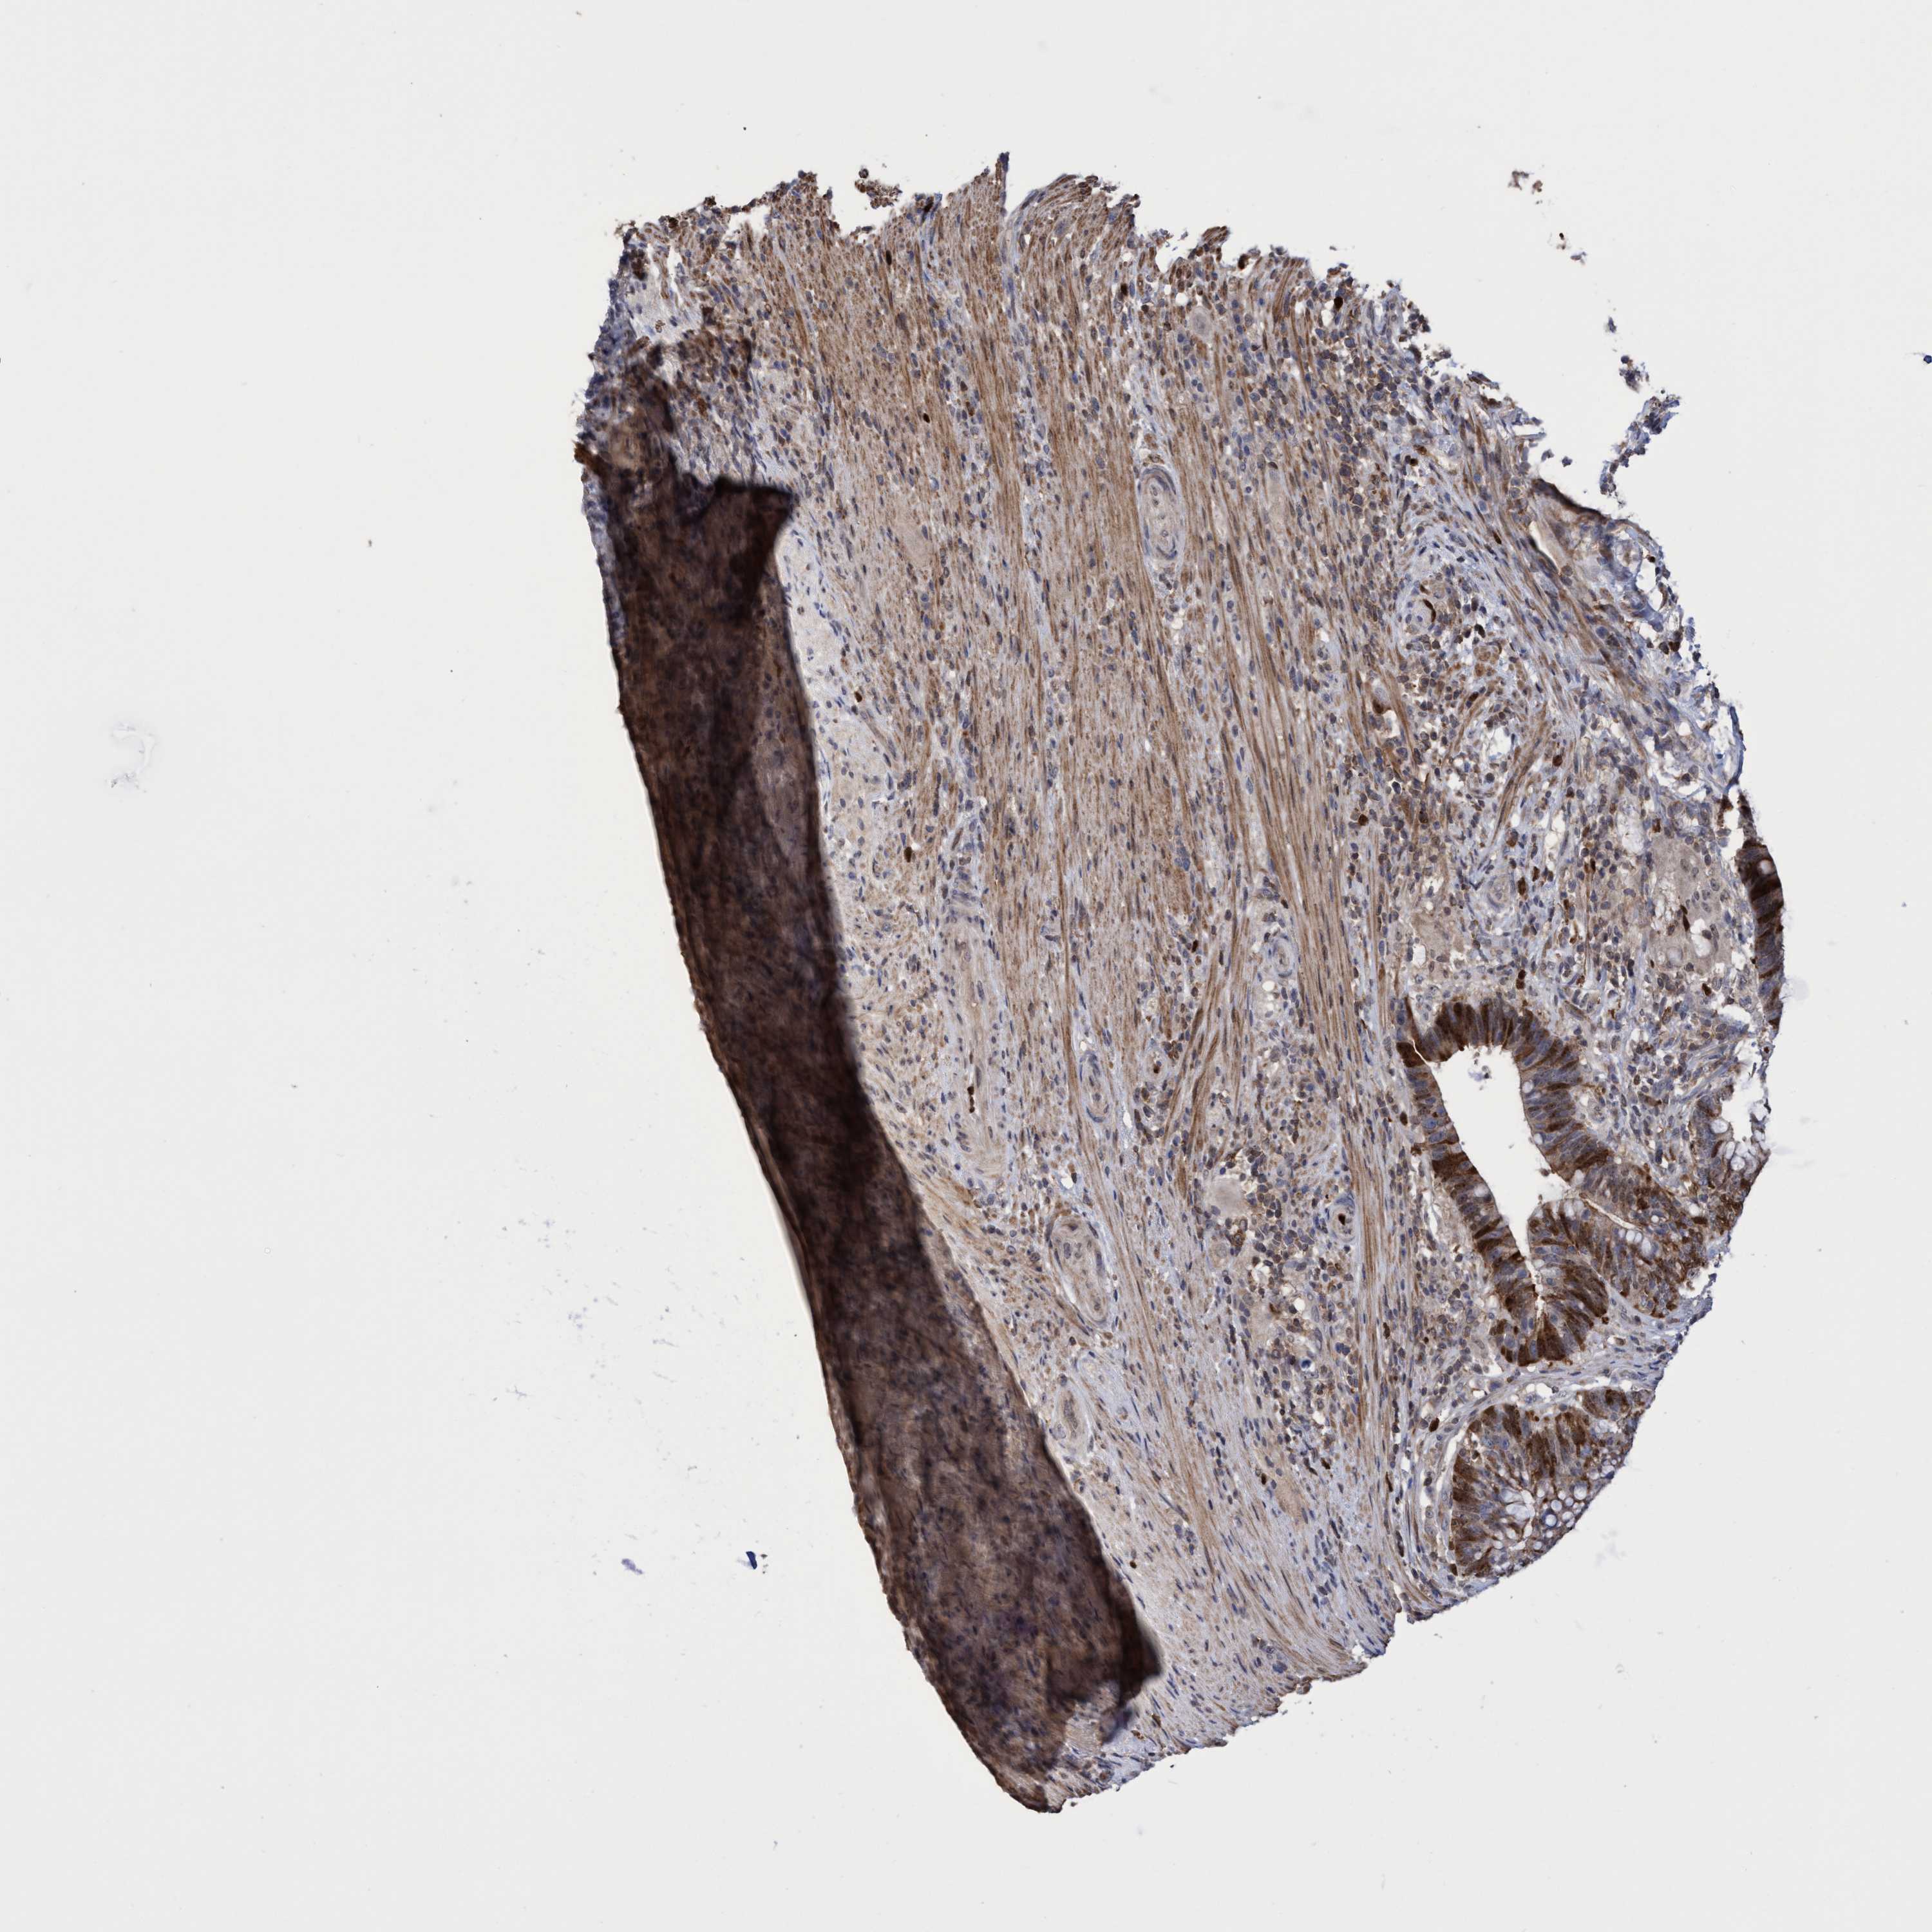

CANCER COLORECTAL CANCER Show tissue menu

Colorectal cancer

Rectum adenocarcinoma